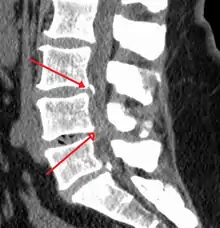

Causes may include osteoarthritis, rheumatoid arthritis, spinal tumors, trauma, Paget's disease of the bone, scoliosis, spondylolisthesis, and the genetic condition achondroplasia.[3] It can be classified by the part of the spine affected into cervical, thoracic, and lumbar stenosis.[2] Lumbar stenosis is the most common, followed by cervical stenosis.[2] Diagnosis is generally based on symptoms and medical imaging.[4]

The most common forms are cervical spinal stenosis, which are at the level of the neck, and lumbar spinal stenosis, at the level of the lower back. Thoracic spinal stenosis, at the level of the mid-back, is much less common.[26]

In lumbar stenosis, the spinal nerve roots in the lower back are compressed which can lead to symptoms of sciatica (tingling, weakness, or numbness that radiates from the low back and into the buttocks and legs).

The diagnosis of spinal stenosis involves a complete evaluation of the spine. The process usually begins with a medical history and physical examination. X-ray and MRI scans are typically used to determine the extent and location of the nerve compression.